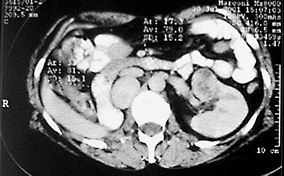

Obr. 1 CT – recidiva v lůžku po nefrektomii a postižení solitární ledviny

Jedná se o 59 letou pacientku. V září 1994 jí byla provedena nefrektomie pro nádor (tumorózní ložisko o průměru 8 cm, histologicky adenokarcinom ledviny s nekrózami a invazí do cév). Na doporučení onkologa podstoupila adjuvantní imunoterapii interferonem alfa. V dalších letech byla nemocná standardním způsobem sledována. Pravidelné kontroly (ultrazvukové vyšetření břicha, scintigrafie skeletu, rtg srdce a plic a CT retroperitonea) nenasvědčovaly o progresi choroby. V červnu 2001 byl ultrazvukem v lůžku po nefrektomii nalezen solidní útvar velikosti 46x39x33 mm, druhé suspektní ložisko se objevilo v kompenzatorně zvětšené levé ledvině. Předoperační diagnózu lokální recidivy a nádorového postižení solitární ledviny jsme potvrdili na CT a angiografickém vyšetření. Zvyklým způsobem jsme vyloučili generalizaci onemocnění. Pacientka byla připravena k operačnímu řešení. V říjnu 2001 jsme revidovali retroperitoneum vpravo. Ve výši pahýlu renální vény retrokaválně jsme nalezli oválný tumor velikosti asi 9x6x6 cm odtlačující dolní dutou žílu mediálně. Útvar se nám podařilo vcelku odstranit. Histologicky byla prokázána recidiva karcinomu z jasných buněk tvořící opouzdřený infiltrát solidně alveolárně uspořádaný, místy prokrvácený. V témže měsíci jsme operovali solitární ledvinu. Provedli jsme resekční záchovný výkon. Resekční linie byly bez nádorové infiltrace. Podle histologického nálezu se jednalo o dobře diferencovaný adenokarcinom ledviny. Po operacích pacientka podstoupila imunochemoterapii podle Atzpodiena na onkologickém oddělení. Kontrolní vyšetření neprokazují progeresi onemocnění. Biochemicky má normální renální funkce.